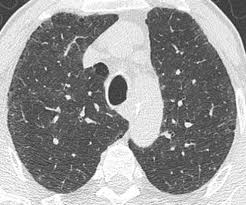

Morphologic classifications of lung conditions diffuse interstitial lung diseases in particular have been undertaken both at the microscopic pathologic patterns and gross radiographic or thin-section computed tomographic CT patterns level. Reticular nodular high and low attenuation table. The lung interstitium is the space where the air sacs called alveoli come in contact with connective tissue and blood vessels to exchange oxygen and carbon dioxide.

In ILDs scarring damages tissues in or around the lungs air sacs and airways. On HRCT there are four patterns.